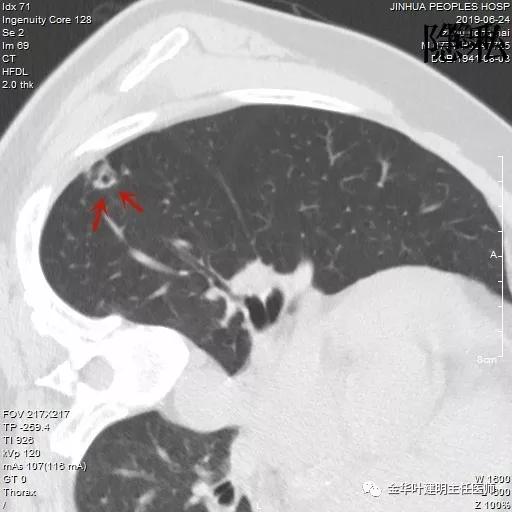

以上是2016年5月的片子,此处有非常小而淡的空腔性病灶,边缘略显磨玻璃,但仍说不上肯定的恶性。